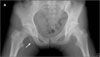

A 13-year-old girl felt a “pop” while doing a split during gymnastics. She later complained of right hip pain and inability to bear weight on the right leg.

Limited range of motion was noted during flexion and internal rotation of the right hip. The patient had pain on palpation over the right ischium and was unable to fully extend her right knee. There was no radiation of pain down the leg and no local bruising or swelling. Anteroposterior (A) and frog-leg (B) radiographs of the pelvis revealed a nondisplaced avulsion fracture of

the right ischial tuberosity.

The radiograph of the acute lesion shows a crescentshaped shadow below or lateral to the ischial physis with varying degrees of separation. In the subacute phase, there is destruction at the fracture site and callus formation that causes a mixed lytic and sclerotic lesion that may mimic an aggressive bone-forming neoplasm (pseudotumor of the ischium), such as Ewing sarcoma, lymphoma, or osteosarcoma.1